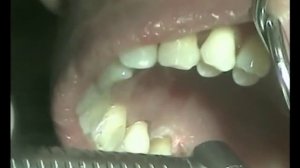

![Лечение пульпита. Как все на самом деле?]() 2:34